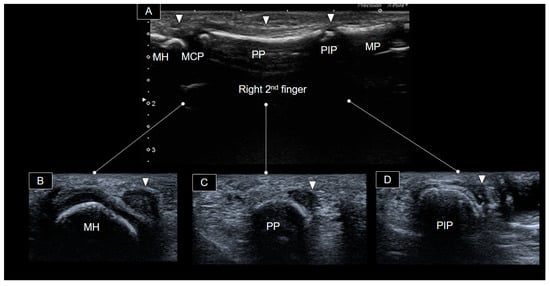

Transverse views of distinct segments of the right second finger, from proximal to distal, are shown in Figure 3.

Figure 3. Ultrasound images depicting the palmar aspect of the right 2nd finger in the long axis (A) and at distinct segments (arrowheads) progressing from proximal to distal in the short axis (BD). MCP, metacarpophalangeal joint; PP, proximal phalanx; PIP, proximal phalangeal joint; MP, middle phalanx; MH, metacarpal head.